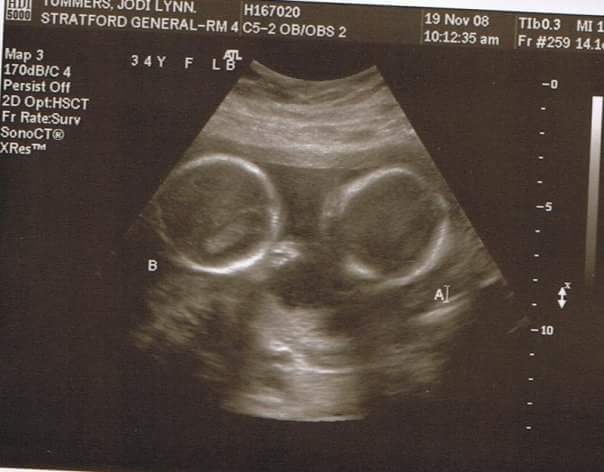

Being pregnant with twins is a moment I don't ever want to forget. I wasn't sure what to include as a photo for this theme day of moments. I decided to include one of the last ultrasounds that I have from before December 10th even though it's not from this actual moment. Those two little round circles in there are my son's Hedge. Too Perfect, wonderful, much wanted and much love little heads, little bodies, little arms and legs, little hands and feet, 20 little toes and 20 little fingers. It's a moment of blessing.